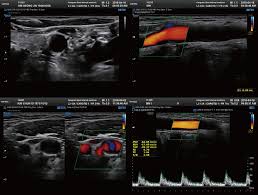

경동맥 초음파 검사는 일반적으로 간단한 과정으로 이루어져 있습니다. 환자는 편안한 자세로 누운 채로 검사가 시작됩니다. 검사자는 초음파 기계를 사용하여 경동맥의 위치에 젤을 바르고, 초음파 송신기를 적용하여 이미지를 생성합니다. 이 과정에서 환자는 특수한 느낌이나 통증을 느끼지 않아야 하며, 검사는 보통 30분 정도 소요됩니다.

검사 후 생성된 이미지를 바탕으로 의사는 동맥의 두께, 협착 여부, 혈전 존재 여부 등을 평가하여 다양한 질병의 가능성을 진단하게 됩니다. 이러한 과정은 고도화된 기술을 활용하여 매우 정확하게 이루어지므로, 정기적인 검사는 매우 중요합니다.

뇌졸중은 뇌로 가는 혈액 공급이 차단되었을 때 발생합니다. 경동맥 초음파 검사를 통해 경동맥의 협착 상태를 확인하면, 뇌졸중의 위험도를 평가하고 예방할 수 있습니다. 만약 경동맥에 심한 협착이 관찰된다면, 이에 따른 치료 및 관리가 필요합니다.